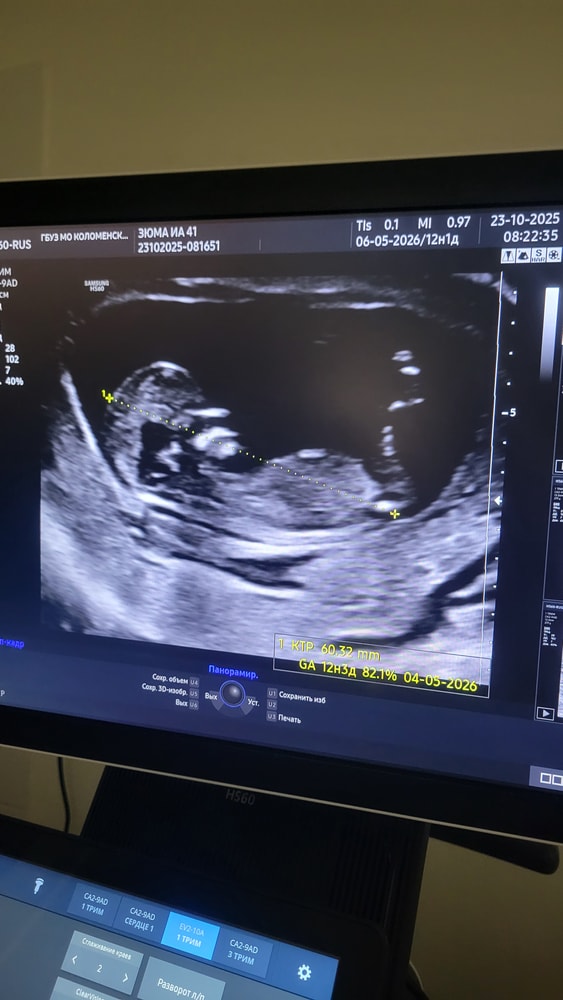

Сынок или дочка? 12 нед и 2 дня

Душевные переживанияПонимаю, что рано, и что здоровье малыша это самое главное, но все же...